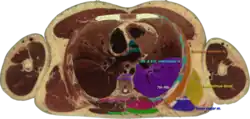

Cross section #1428 of the Visible Human Male showing the structures of the triangle of auscultation

The superficial floor of the triangle is formed by the lateral portion of the erector spinae muscles. Deep to these muscles are the osseous portions of the 6th and 7th ribs and the internal and external intercostal muscles.

The triangle of auscultation is useful for assessment using a pulmonary auscultation and thoracic procedures.[1] Due to the relative thinning of the musculature of the back in the triangle, the posterior thoracic wall is closer to the skin surface, making respiratory sounds audible more clearly with a stethoscope. On the left side, the cardiac orifice of the stomach lies deep to the triangle. In days before X-rays were discovered, the sound of swallowed liquids were auscultated over this triangle to confirm an oesophageal tumour. To better expose the floor of the triangle up of the posterior thoracic wall in the 6th and 7th intercostal space, a patient is asked to fold their arms across their chest, laterally rotating the scapulae, while bending forward at the trunk, somewhat resembling the fetal position.